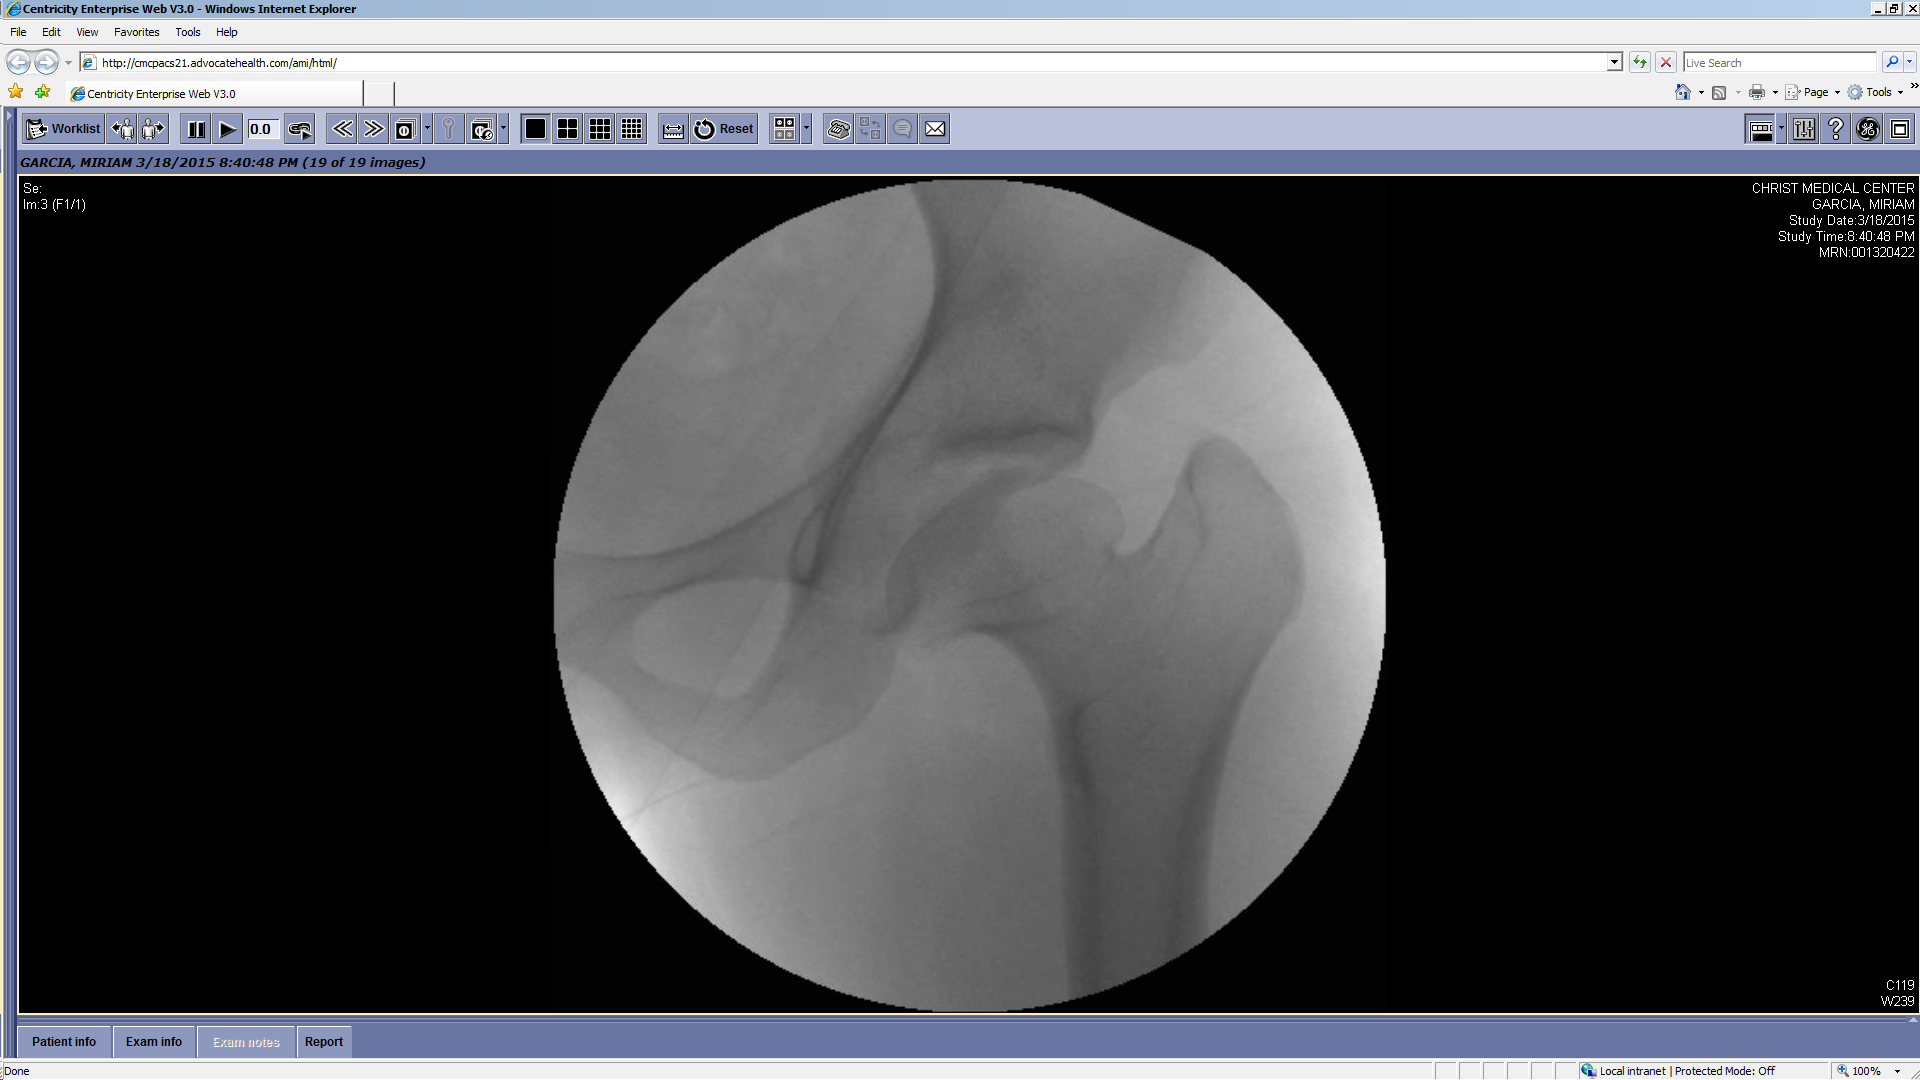

Treatment

Treatment can be selective — identifying and treating the most likely cause of hip pain and dysfunction — or comprehensive, correcting all potential causes in one stage. Dr. Prasad Gourineni performs arthroscopic evaluation and correction of mild asphericity of the head or acetabular retroversion when the remaining morphological variations are mild and unlikely to cause symptoms. In more severe deformities, all abnormalities are corrected with the surgical dislocation approach, which allows head reshaping, neck lengthening, greater trochanter transfer, and acetabuloplasty.